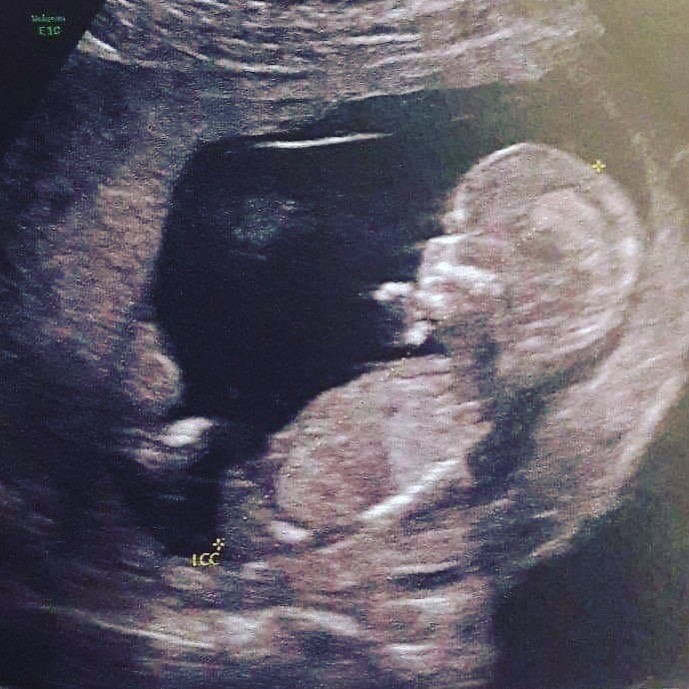

Fizemos a ecografia do primeiro trimestre quase no último dia recomendado, tudo porque as férias de Natal, para Portugal, já estavam marcadas. E se o meu médico ginecologista na altura tinha desvalorizado o facto de fazer a ecografia "no limite do tempo", já o mesmo não aconteceu no dia da ecografia... O médico não achou muito correcto fazer a ecografia às 13 semanas e 6 dias porque a colheita de sangue, que permite fazer o rastreio das anomalias cromossómicas (as chamadas trissomia 13, 18 e 21), deveria ser realizada até às 13 semanas e 6 dias, e como a ecografia foi feita no final do dia, as ditas análises só foram feitas no dia seguinte...

Ainda chegamos a pensar que iríamos saber o sexo do nosso bebezinho naquele dia, mas o médico disse que ainda não dava para ter certeza de nada, por isso nem um palpite quis dar... O engraçado é que durante o procedimento eu e o R. vimos um Principezinho a olhar para nós... (Lol...)